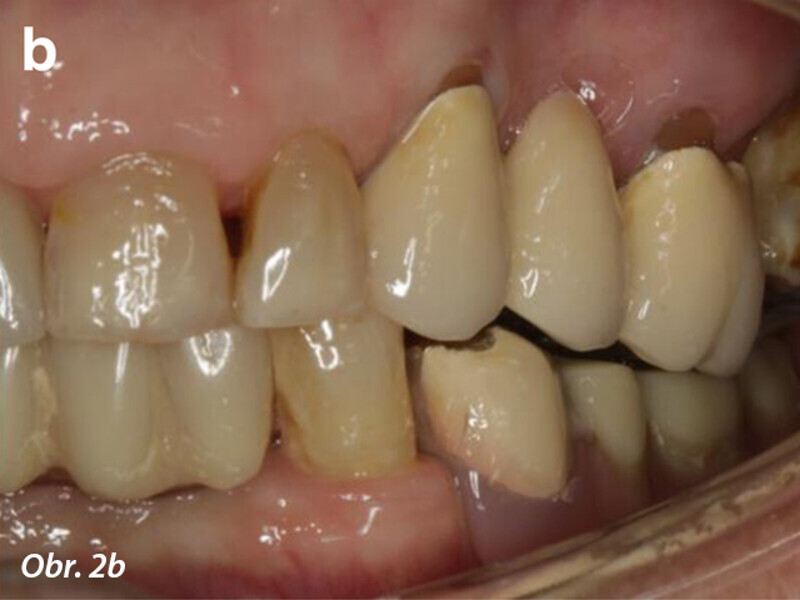

Počítačem asistované, šablonou se řídící okamžité zavedení a zatížení implantátu v dolní čelisti